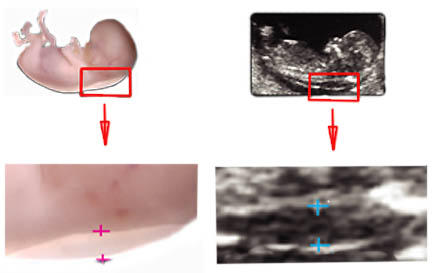

Помимо стандартного исследования УЗИ с наблюдением ручек-ножек, позвоночника, формирования мозга, измеряют так называемую воротничковую зону. Воротничковая (воротниковая) зона – это зона в области шеи между кожей и мягкими тканями, в которой скапливается жидкость. Сильное превышение показателей над нормой может говорить об отклонениях в развитии плода.

Нормы воротничковой зоны определяются в зависимости от возраста эмбриона, так как она сильно меняется. Средняя толщина воротничковой зоны — 0,12 см в 11 недель (нормой принято считать толщину до 2 мм) и 0,15 см в 14 недель (к норме относят толщину до 2,6 мм).

ВНИМАНИЕ! Измерение воротничковой зоны требует очень квалифицированных операторов со специальной подготовкой. Без дополнительных исследований постановка диагноза только по результатам УЗИ невозможна!